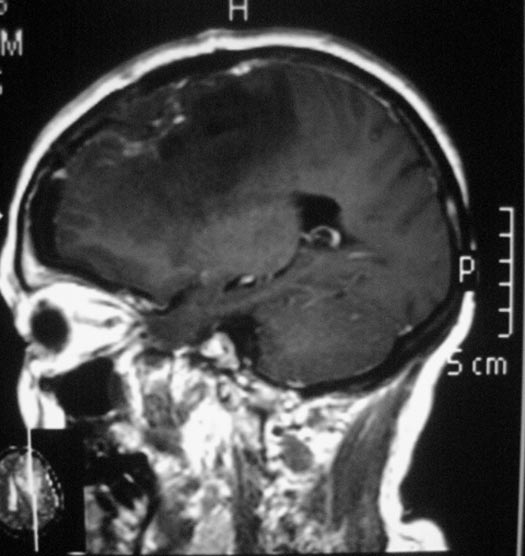

惴惴不安地去医院检查,CT结果提示:左侧额部占位,考虑脑膜瘤可能性大。广东三九脑科医院头颅MR检查提示肿瘤大小为:44.9mm×42.5mm×38.2mm。

完善相关检查后,综合神经外科的鲁明主任主刀在全麻下行左侧额部镰窦旁凸面脑膜瘤切除术,术中导航定位肿瘤体表投影,显微镜下见灰白色肿瘤组织,血供丰富,边界清楚,周围脑组织水肿软化,肿瘤未与大脑镰粘连,分离后予肿瘤全切,肿瘤边缘硬膜予以扩大切除,镜下达辛普森I级切除。手术后,林阿姨的术前症状都已消失,没有出现任何术后并发症。术后病理结果为:上皮型脑膜瘤。